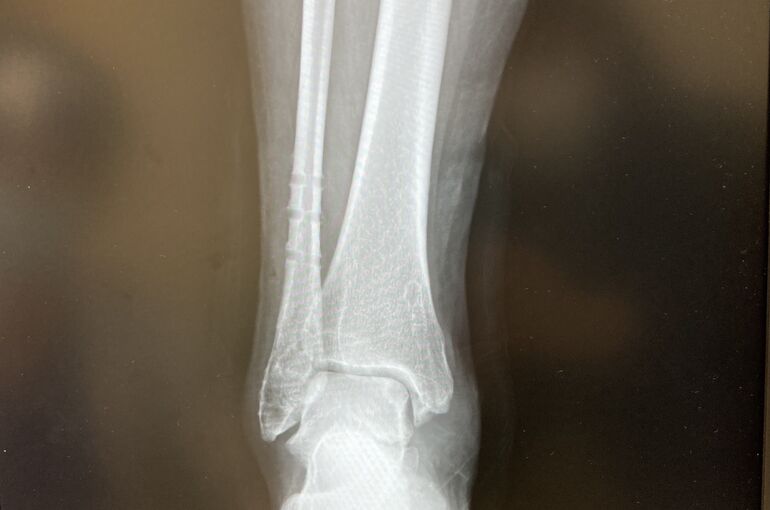

2枚目の写真、骨折して手術をして、プレートとボルトで固定したエックス線(レントゲン)写真。